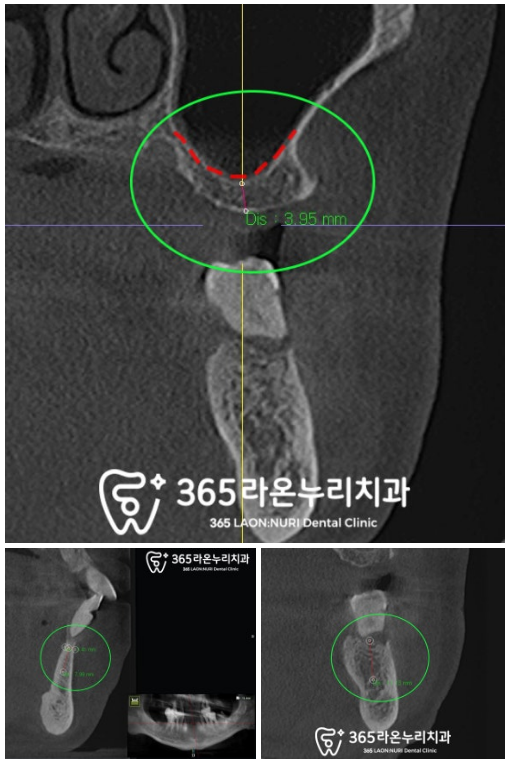

아무래도 파노라마에서 보기에는

입체적이지 못하여

정확도가 떨어지기에

3D CT를 찍어보았는데요,

오른쪽 위 어금니가

예상했던 것보다 좋지 않았습니다.

말씀드렸던 대로

순차적으로 이를 빼고

그 자리에 픽스처를 심기 위하여

남은 뼈의 높이를 확인하는 과정입니다.

잔존골의 양이 부족한 곳은

인공뼈를 추가로 이식해 드리고

안전한 식립을 위하여

치조골의 폭경을 체크하고 있는

모습이랍니다.